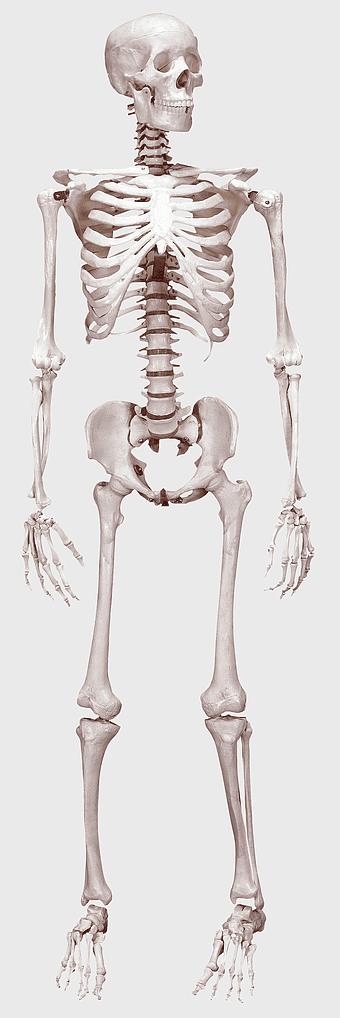

Human skeleton, human body anatomy, standing skeleton, bone structure, skeletal system, medical illustration, human anatomy study -